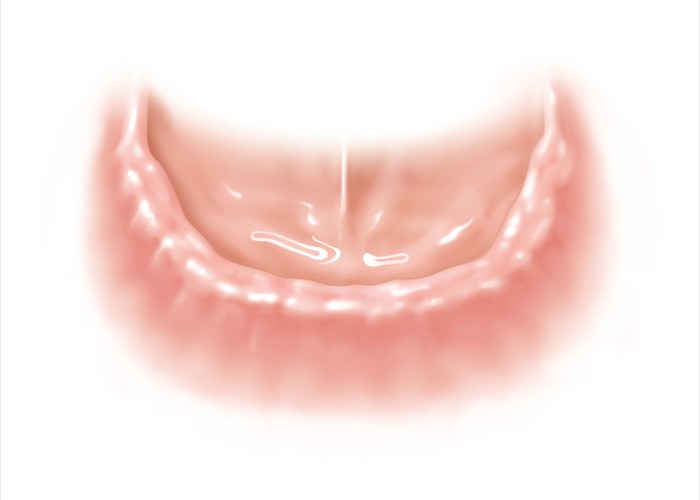

Zahnloser Unterkiefer. Die hier normalerweise übliche Totalprothese hält meist nicht besonders gut.

Zahnloser Unterkiefer. Die hier normalerweise übliche Totalprothese hält meist nicht besonders gut.